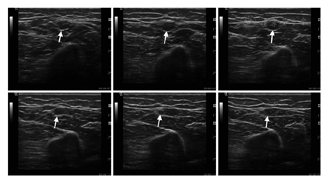

高频神经超声测定时患者可以取坐位或卧位,肢体放松,不同神经测定时放置姿势有所不同,以患者舒适、且操作者易于操作为原则。检测过程主要从两个角度对周围神经进行评估,包括垂直于神经走行的横截面和平行于神经走行的纵切面。在正常周围神经,横截面表现为蜂窝样结构,包括低信号的神经纤维束和高信号的神经束膜,以及高信号的神经外膜(图10A);纵切面则表现为轨道样或线样的平行神经束,以及高信号的神经外膜(图10B)。在周围神经近端以及臂丛,神经超声的信号可以呈现为较均一的低信号结构,而缺乏蜂巢样特点,与近端神经的神经束密集而结缔组织减少有关[20]。